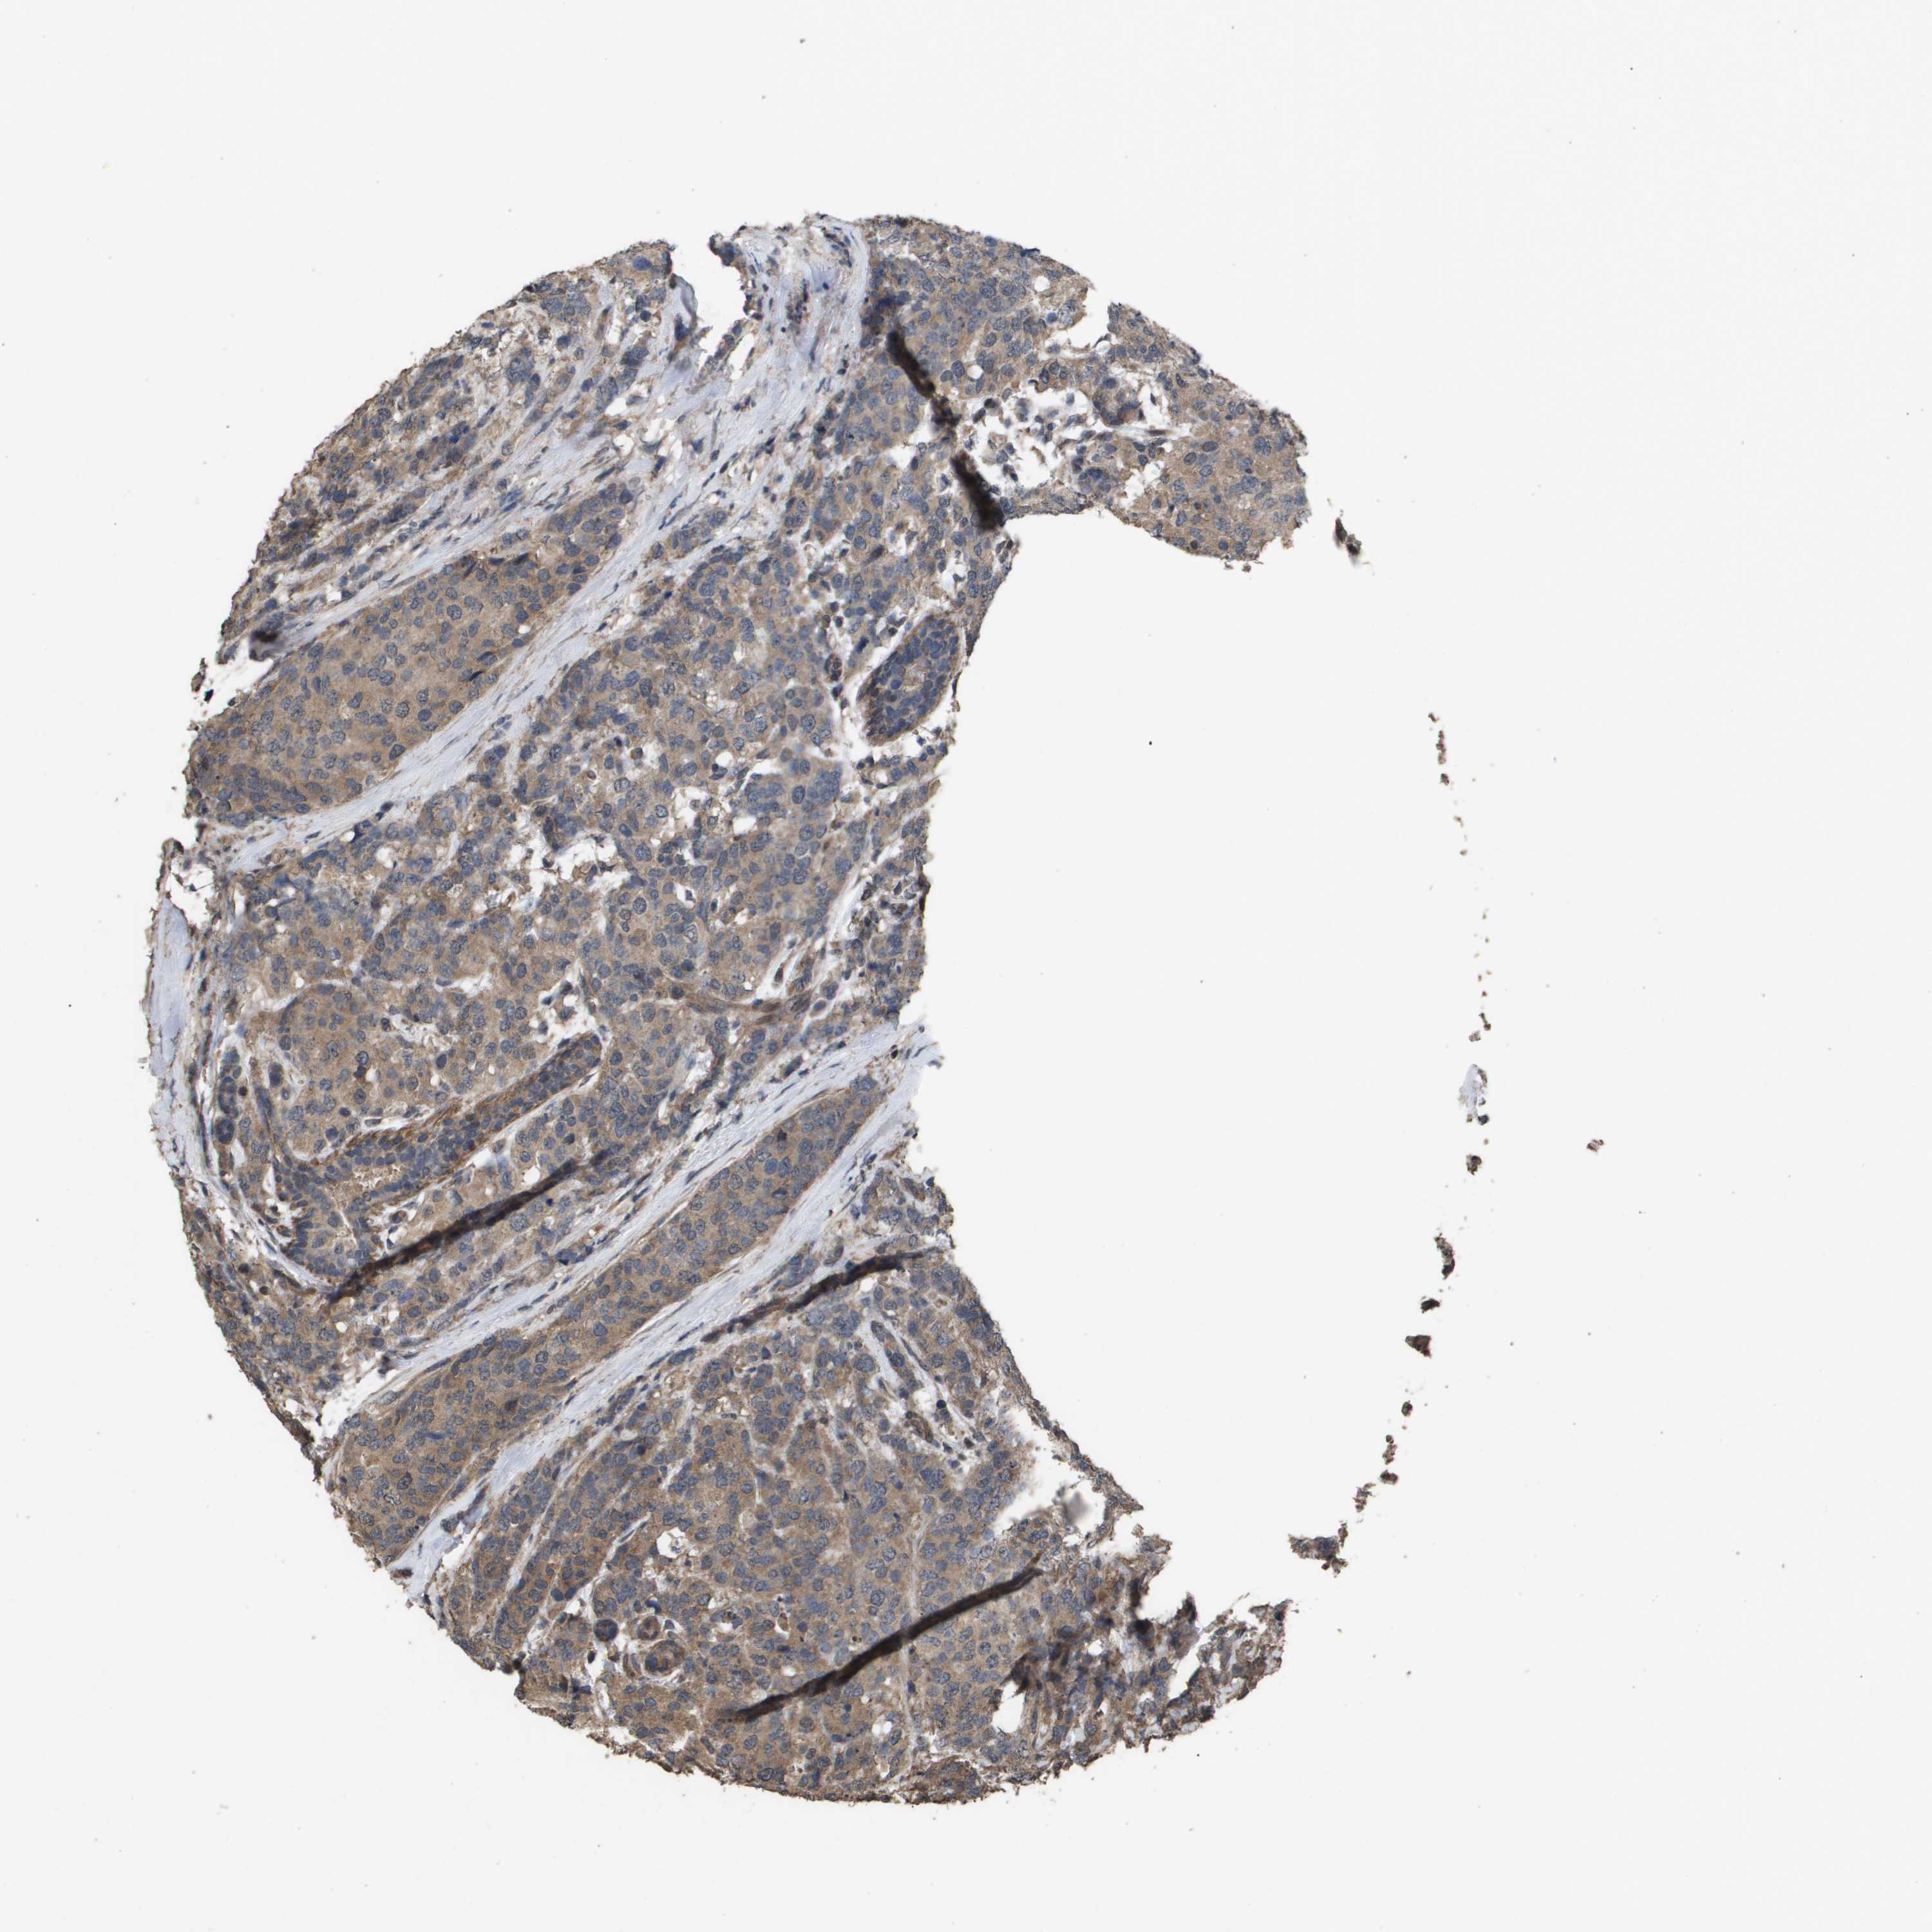

BRCA TCGA BRCA VALIDATION PROTEIN EXPRESSION